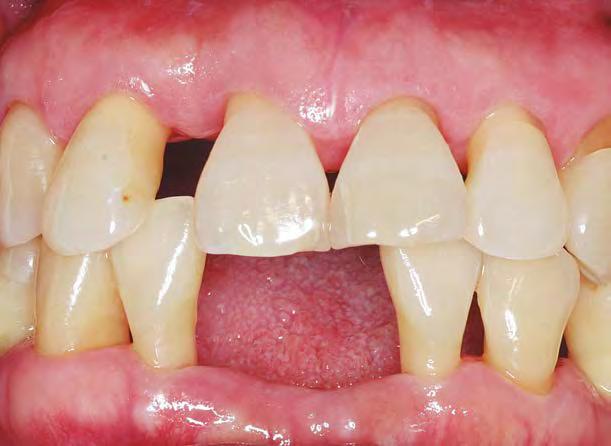

–MARPE, una alternativa a la disyunción en el paciente adulto, por el Dr. Enrique Solano y cols. [88]